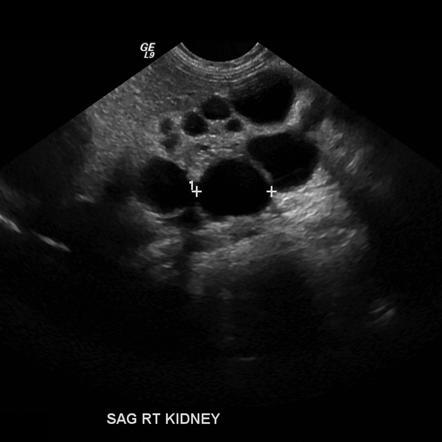

Newborn with a hypoechoic lesion on ultrasound

A

MESOBLASTIC NEPHROMA.

Wilms like tumor, but <1 month old.

Solid renal tumor of infancy. Fetal hamartoma. Most common renal tumor in the first month of life.Involves renal sinus.